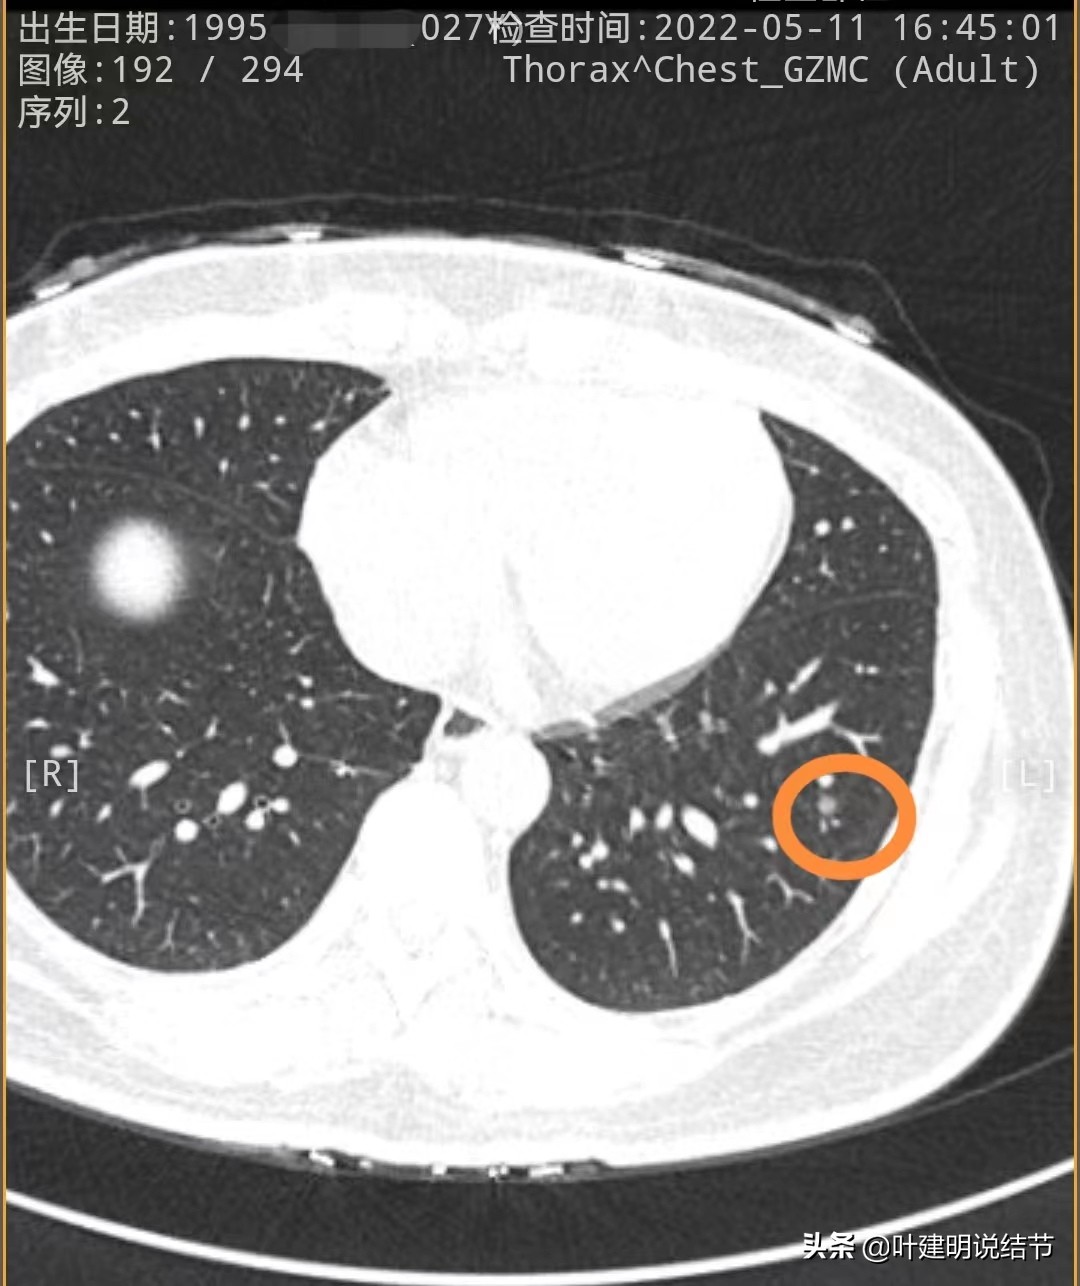

先来看2020年时的CT图像:

左下叶淡磨玻璃结节,轮廓较清,没有实性成分,以不典型增生可能性为大些

左上叶舌段密度偏高结节,边界较清,原位癌可能,也可以是良性结节,边缘膨胀性略差

左下叶另一结节,密度低,轮廓 也清,考虑腺体胶驱病变,不典型增生或原位癌可能性大些

再来看今年2022年的片子:

左下第一处结节几乎没有明显变化

左上舌段结节感觉略圆起来一点,但大小说不上显著增大进展,轮廓清

左下另一处结节感觉略有进展,但总体应该仍是原位癌可能性大些。